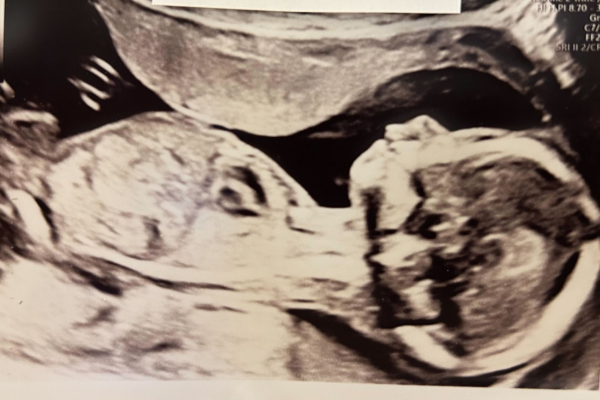

Uge 18+0 – 18+6

Barnet i maven vokser nu hurtig og vejer omkring 230 gram. Det måler cirka 18 cm. Ørerne har flyttet sig derhen, hvor de skal sidde resten af livet, og stikker nu lidt ud fra hovedet. Øjnene er kommet tættere på forsiden af ansigtet, og de omgives af øjenbryn og en antydning af vipper. Under de lukkede øjenlåg er nethinden blevet klar, og den kan nu reagere på lys. De små knogler i øret er forbenet nok til, at den lille kan høre dit hjerteslag, blodet der bruser i dine årer og tarmene, der arbejder. Jo ældre fostret bliver, jo mere kan det høre. Barnet kan også høre forskel på mors, fars og søskendes stemmer. Musik og jeres stemmer virker beroligende. Du kan spille musik for barnet, som det kan genkende og føler sig tryg ved, når det er født. Barnet gør også klar til at se. Selvom øjnene er lukkede frem til uge 25-28, kan den lille fornemme forskellen mellem lys og mørke. Dit barn er aktivt nu og skifter stilling mange gange om dagen.

En tidlig misdannelsesscanning kan laves nu. Har I sygdomme i familien, eller er du bekymret for dit barns udvikling, kan en tidlig misdannelsesscanning ofte skabe tryghed.